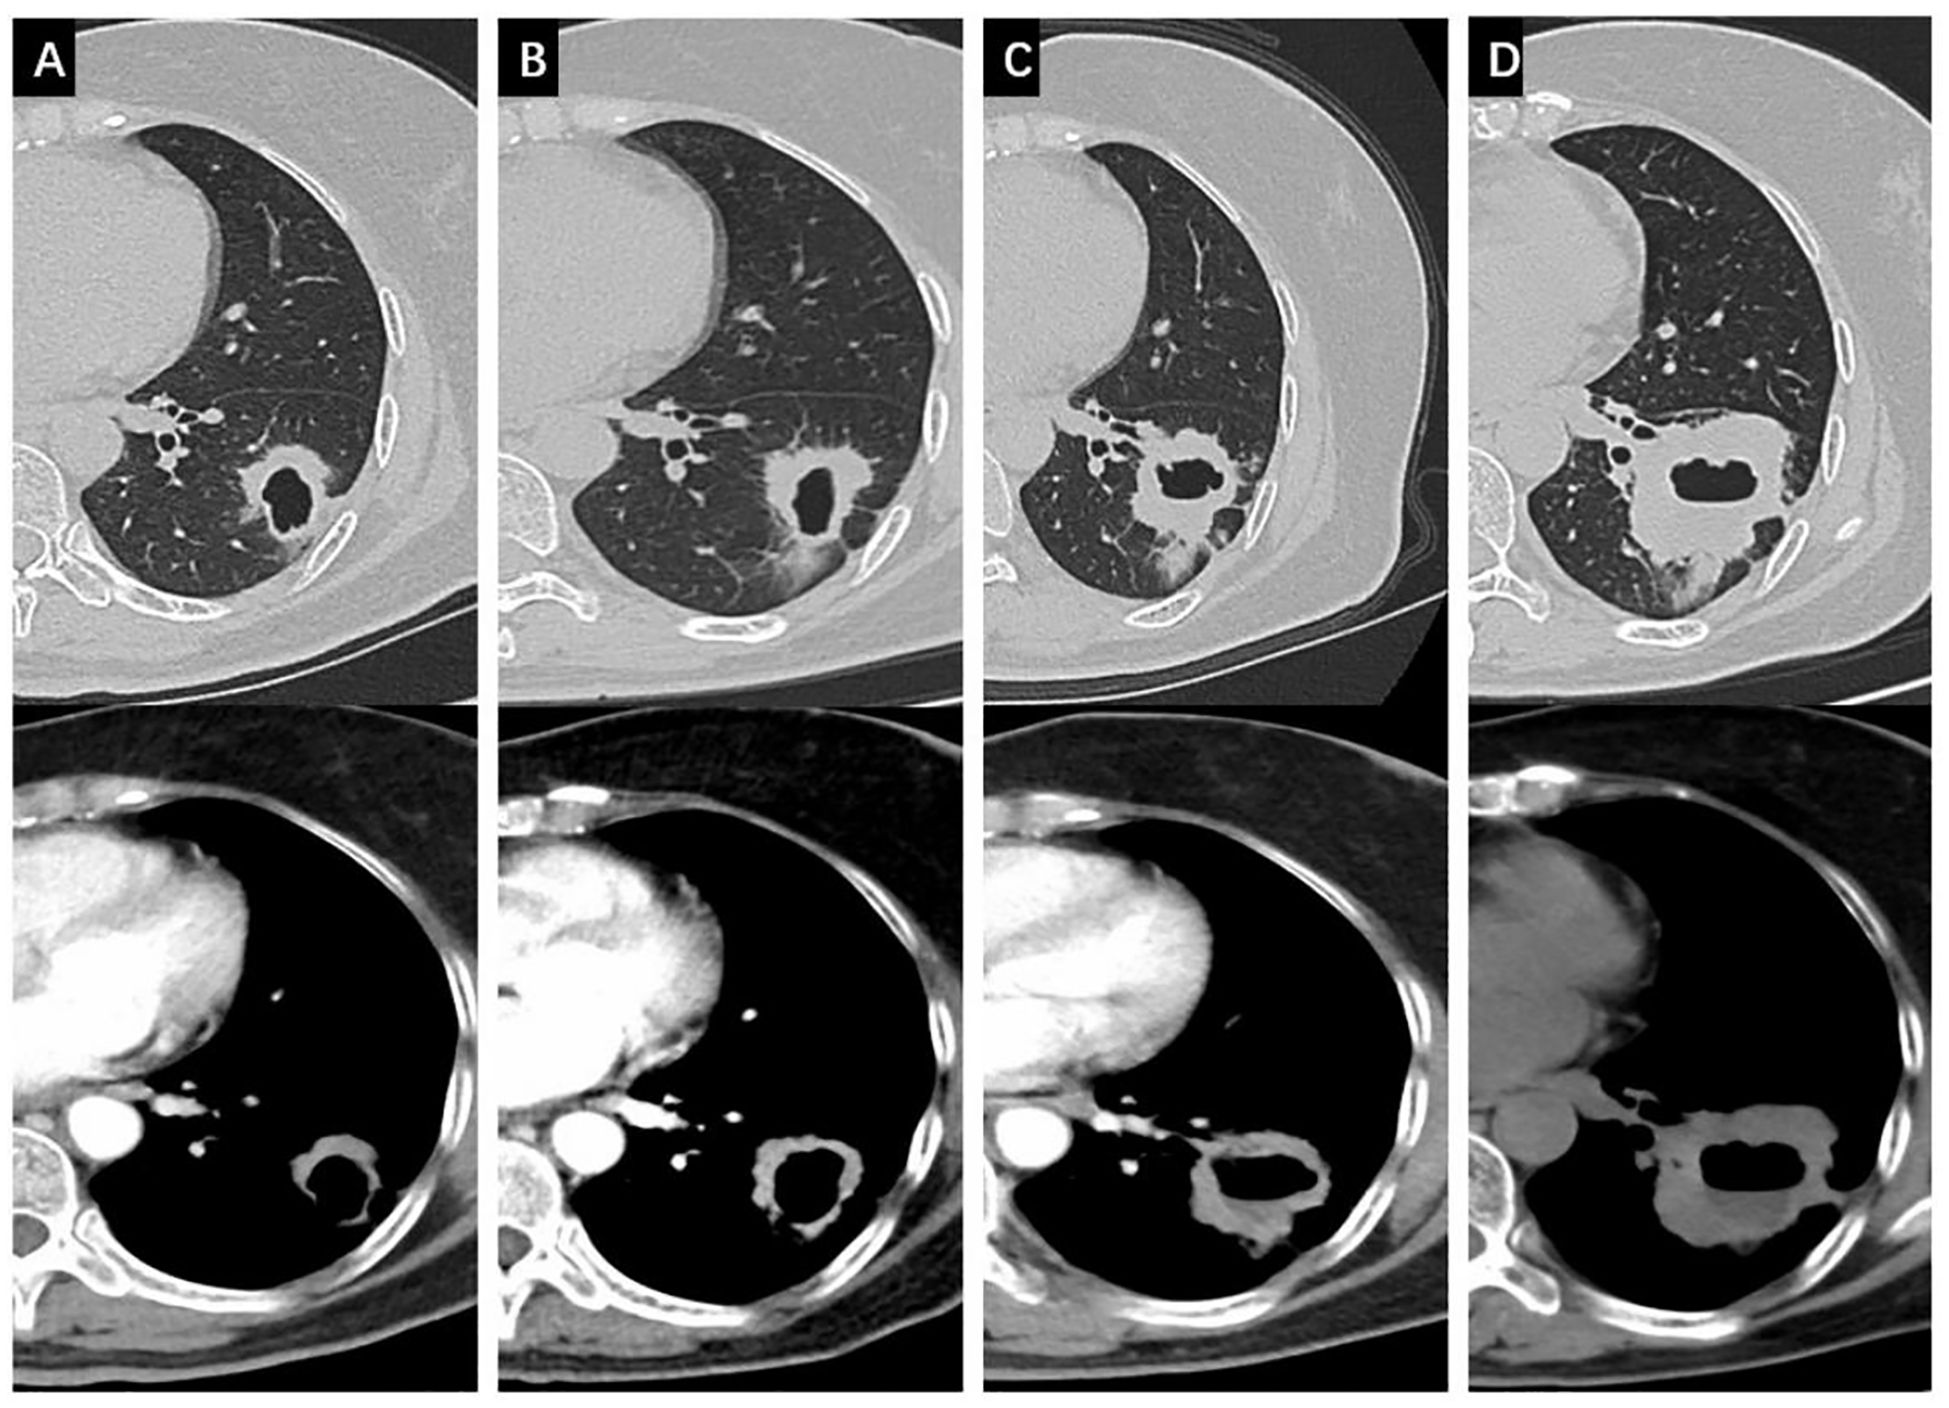

Osimertinib was used as the first-line therapy. One month later, follow-up CT showed remission of both the primary lesion (29 x 20 mm) and lymph node, with continued shrinkage for over 14 months (18 x 12 mm). However, after 16 months, resistance to osimertinib developed, and follow-up CT showed a new metastatic lesion at the right diaphragmatic angle (Figure 3) as well as in mediastinal lymph nodes. The disease was staged as cT1bN2M1a (IVA). Six cycles of chemotherapy (Taxol + Platinum, TP) combined with immune checkpoint inhibitor (Tislelizumab) therapy were applied, and the disease maintained stable with an OS of 31 months to date.

Figure 3

Four panels labeled A to D show axial CT images of lung sections in two rows. The top row images highlight the lung's structure with clear air spaces and vascular markings. The bottom row images use contrast to enhance vascular and tissue details, providing a different visual representation of the same sections.

Figure 3. Changes of the non-cavitated SqCLC in the right middle lobe in both the lung window and the mediastinal window. (A) baseline CT before osimertinib treatment; (B) changes of the primary lesion after 1 months of osimertinib; (C) changes of the primary lesion after 14 months of osimertinib; (D) changes of the primary lesion after 16 months of osimertinib with a newly emerged lesion in the right diaphragmatic angle.